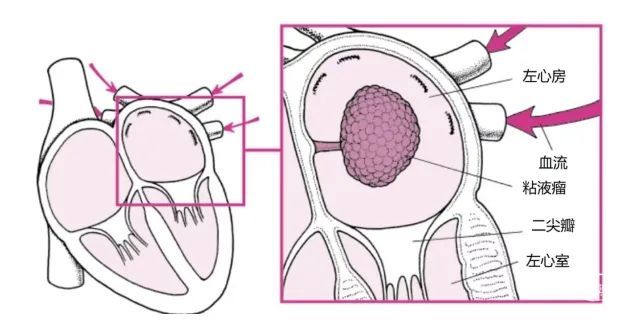

粘液瘤不是癌症,但仍然是危险的,因为它们会干扰你的心脏功能。这就是为什么患有粘液瘤的人需要手术切除肿瘤并防止严重并发症的原因。

瓣膜处梗阻。粘液瘤的主体通常长在一根茎上,可以随血液流动和心脏收缩在心腔内来回摆动。如果粘液瘤进入瓣膜开口,它会暂时影响、甚至阻断通过瓣膜的血液流动,可以产生血压波动、晕厥,甚至危及生命的严重后果。这通常发生在左心房和左心室之间的心脏瓣膜——二尖瓣。